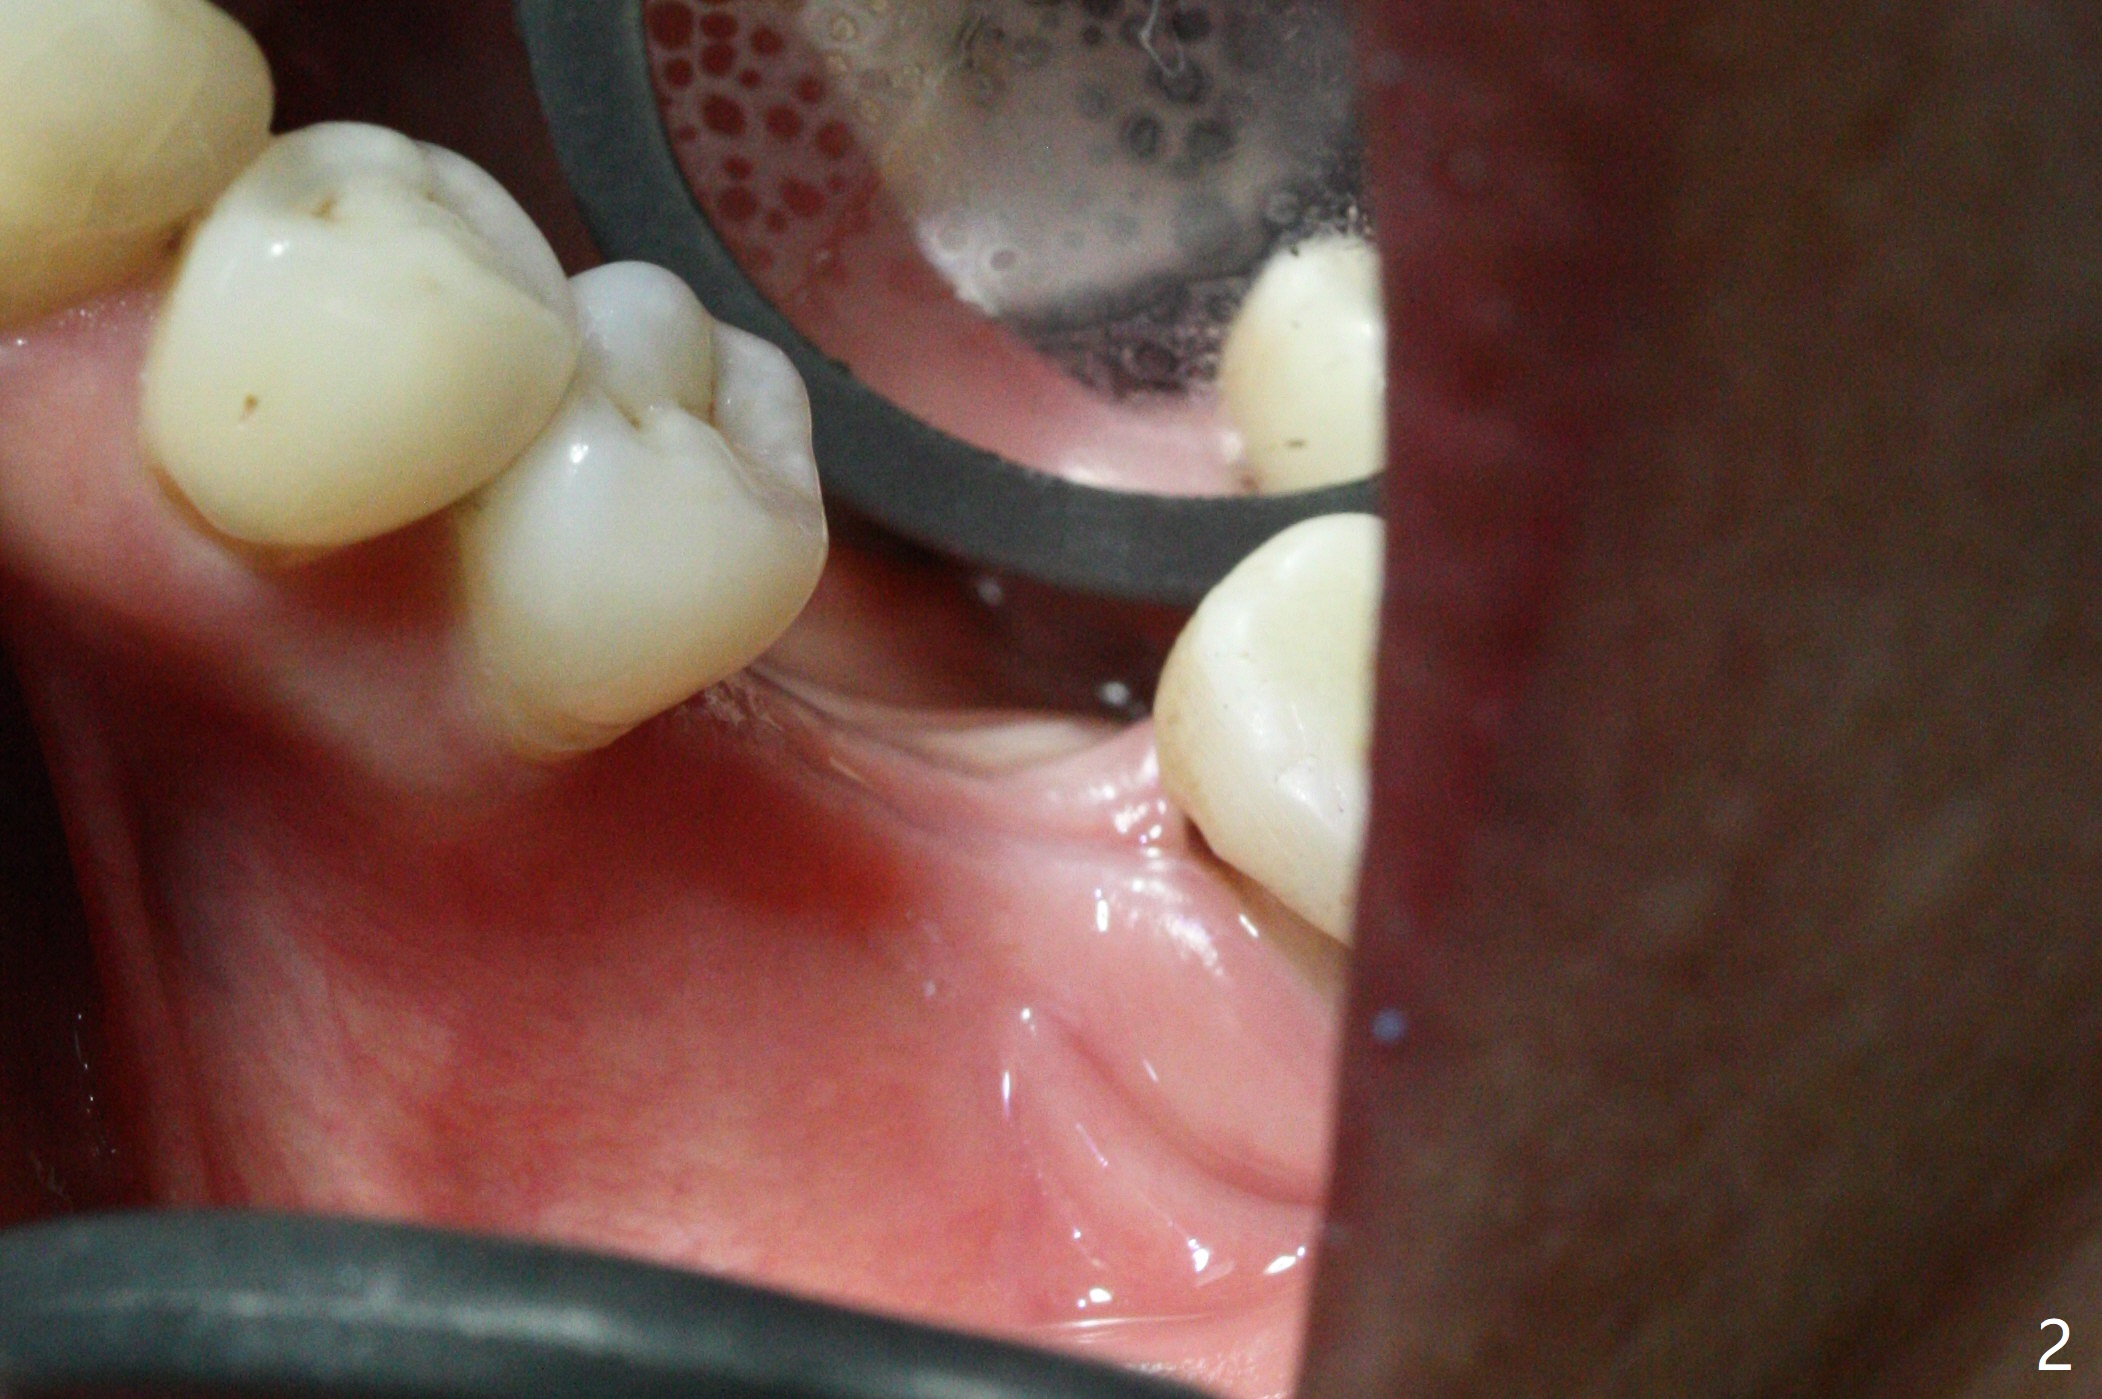

CT taken 4-5 months post extraction shows the outline of the socket at #19 (Fig.1 pink and red dashed line). By the time of surgery (6-7 months post extraction), the ridge looks narrow (Fig.2). In fact the socket does not heal (Fig.3). Osteotomy starts at the mesial border of the socket (Fig.4). When a 5x10 mm dummy implant is placed, the axis begins to be tilted distally (Fig.5 red line), which is more obvious when a definitive longer implant (5x11.5 mm) is placed (Fig.6,7). Osteotomy (Fig.1 arrow) at the mesial slope of the socket (red dashed line) should be initiated more mesial to compensate for the distal drifting while osteotomy is being increased and the implant is being placed. The distal defect is filled with Vanilla graft. Probably due to the mesial slope and the distal defect, the primary stability is <10 Ncm. A healing screw is placed with Vanilla allograft/autogenous bone. The bone forms coronal to the implant 4 months postop (Fig.8 *), which is removed for uncover. The mesial gingival embrasure of the permanent crown is large (Fig.9 *), as related to the mesial undercut associated with a 5.7x4 mm A 15 degree angled abutment (Fig.10). Reduction in the undercut should be able to help lab decrease the gingival embrasure (Fig.11 red line). The bone density around the implant increases with distinct trabecular pattern consistent with stress 5 months post cementation (1 year postop, Fig.12).